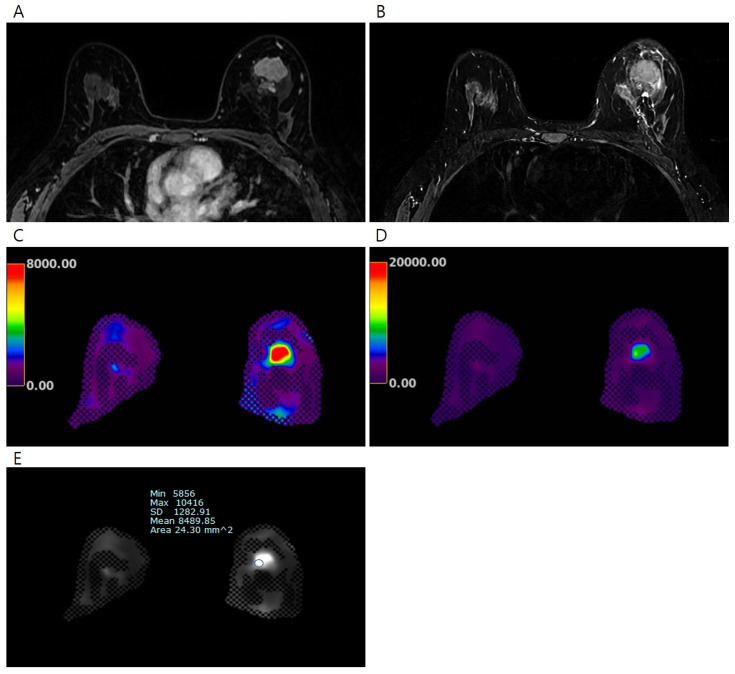

目的:利用磁共振弹性成像(MRE)评估乳腺组织的弹性值,探讨浸润性乳腺癌弹性值与预后因素和新辅助全身治疗(NST)的病理反应之间的关系。方法:前瞻性纳入57例超声检查直径大于2cm的浸润性乳腺癌患者(平均年龄54.1岁)。采用商用声学驱动器通过MRE测量浸润性乳腺癌、正常纤维腺组织和正常脂肪组织的弹性值(平均值、最小值和最大值)并进行比较。根据术前接受NST的患者的预后因素和病理反应比较乳腺癌的弹性值。采用受试者工作曲线分析来评价弹性值对病理反应的预测作用。结果:57例浸润性乳腺癌患者的平均弹性值明显高于正常纤维腺组织和正常脂肪组织(7.90±5.80 kPa vs. 2.54±0.80 kPa vs. 1.32±0.33 kPa, ps均< 0.001)。大直径浸润性乳腺癌(> ~ 4cm)的平均弹性值明显高于小直径肿瘤(≤4cm)(11.65±7.22 kPa vs. 5.87±3.58 kPa, p = 0.002)。在24例接受NST治疗的患者中,病理完全缓解(pCR)组和非pCR组的平均、最小和最大弹性值差异有统计学意义(均p < 0.05)。对于平均弹性值,区分pCR组和非pCR组的曲线下面积为0.880(95%可信区间为0.682,0.976;P < 0.001)。结论:通过乳腺MRE测量的浸润性乳腺癌的弹性值与肿瘤大小呈正相关,具有预测NST患者治疗反应的潜力。

Objectives: To assess the elasticity values in breast tissues using magnetic resonance elastography (MRE) and examine the association between elasticity values of invasive breast cancer with prognostic factors and the pathologic response to neoadjuvant systemic therapy (NST). Methods: A total of 57 patients (mean age, 54.1 years) with invasive breast cancers larger than 2 cm in diameter on ultrasound were prospectively enrolled. The elasticity values (mean, minimum, and maximum) of invasive breast cancers, normal fibroglandular tissues, and normal fat tissues were measured via MRE using a commercially available acoustic driver and compared. Elasticity values of breast cancers were compared according to prognostic factors and pathologic responses in patients who received NST before surgery. Receiver operating curve analysis was performed to evaluate the predictive efficacy of elasticity values in terms of pathological response. Results: Among the 57 patients, the mean elasticity value of invasive breast cancers was significantly higher than that of normal fibroglandular tissue and normal fat tissue (7.90 ± 5.80 kPa vs. 2.54 ± 0.80 kPa vs. 1.32 ± 0.33 kPa, all ps < 0.001). Invasive breast cancers with a large diameter (>4 cm) exhibited significantly higher mean elasticity values relative to tumors with a small diameter (≤4 cm) (11.65 ± 7.22 kPa vs. 5.87 ± 3.58 kPa, p = 0.002). Among 24 patients who received NST, mean, minimum, and maximum elasticity values significantly differed between the pathologic complete response (pCR) and non-pCR groups (all ps < 0.05). For the mean elasticity value, the area under the curve value for distinguishing pCR and non-pCR groups was 0.880 (95% confidence interval, 0.682, 0.976; p < 0.001). Conclusions: The elasticity values of invasive breast cancers measured via breast MRE showed a positive correlation with tumor size and showed potential in predicting the therapeutic response in patients receiving NST.